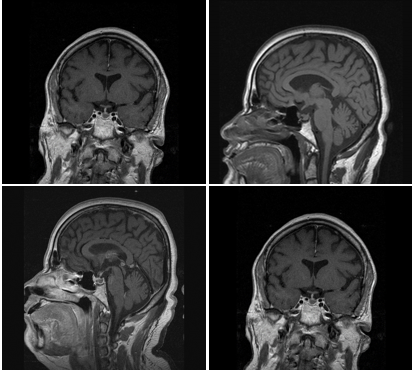

• Surgical Procedure

• The trans-Nasal approach was used, and the ENT Surgeon gained access to the Sella, eventually, the action was taken by the Neurosurgeon who could open the Sella and perform the hypophysectomy (Figure 6).

• The patient appeared to tolerate the procedure well and underwent an uneventful recovery (Figure 6).

Figure 6 Trans-nasal approach (left & Middle), trans-cranial (Right) for resection of CP.courtesy of Aaron Cohn-gadol.com and neurosurgicalatlas.com.